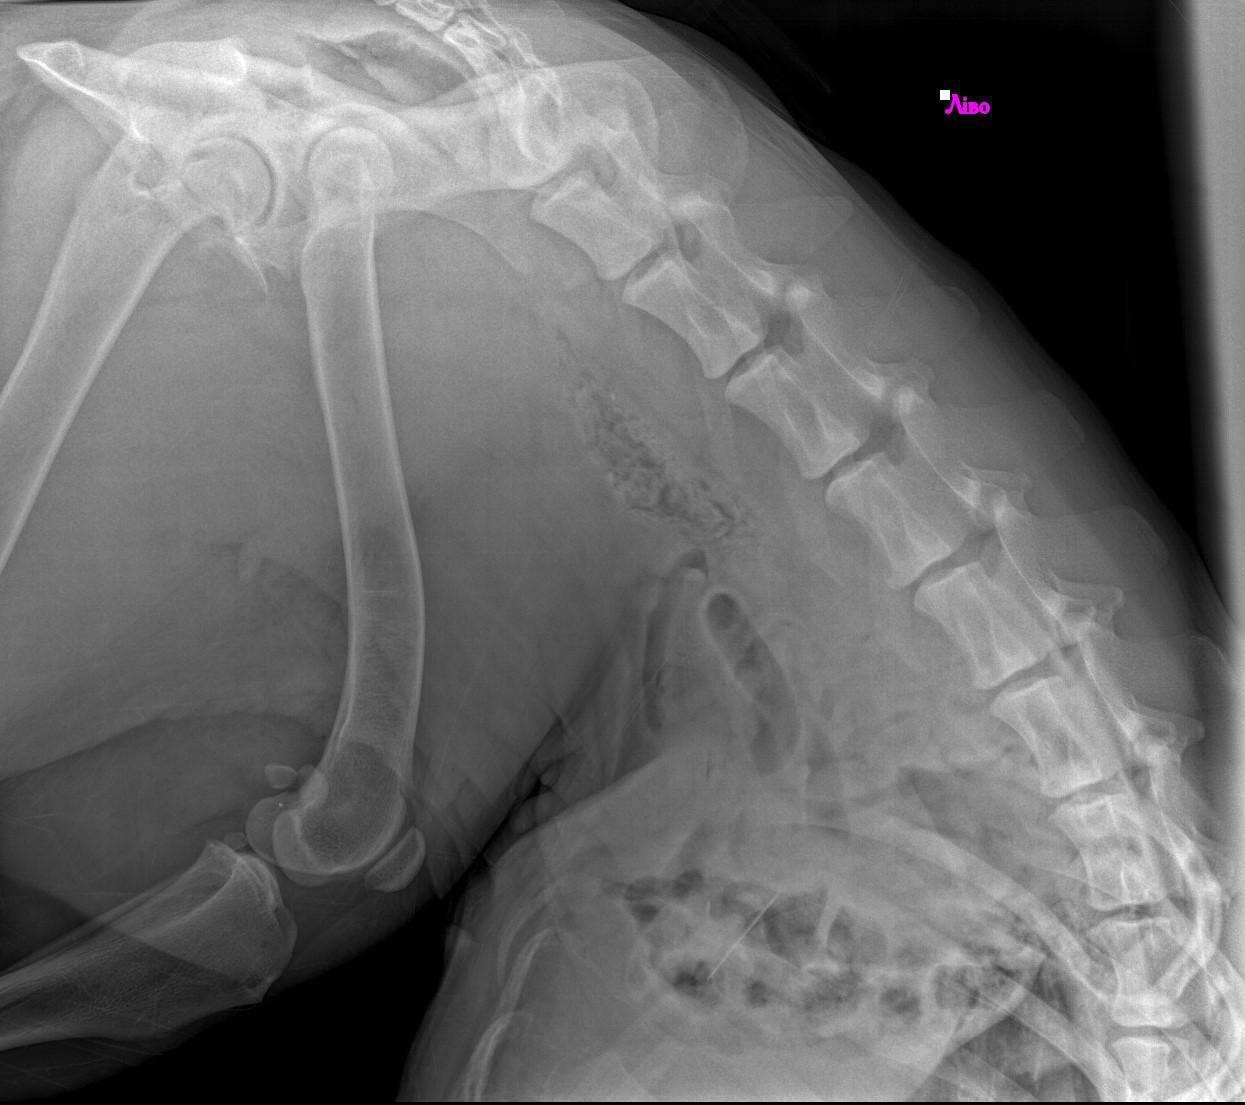

Miała w ciele kulę. Rana była otwarta, krwawiąca. A mimo to… żyła.

Podczas badań okazało się, że oprócz rany postrzałowej, w jej żołądku tkwi igła.

A to nie wszystko – miała też ropne zapalenie macicy, chorobę, która w takim stanie zabija błyskawicznie.

Kula trafiła na stół operacyjny.

Zespół weterynarzy pracował godzinami, ostrożnie, z nadzieją, że jej ciało wytrzyma kolejną próbę.